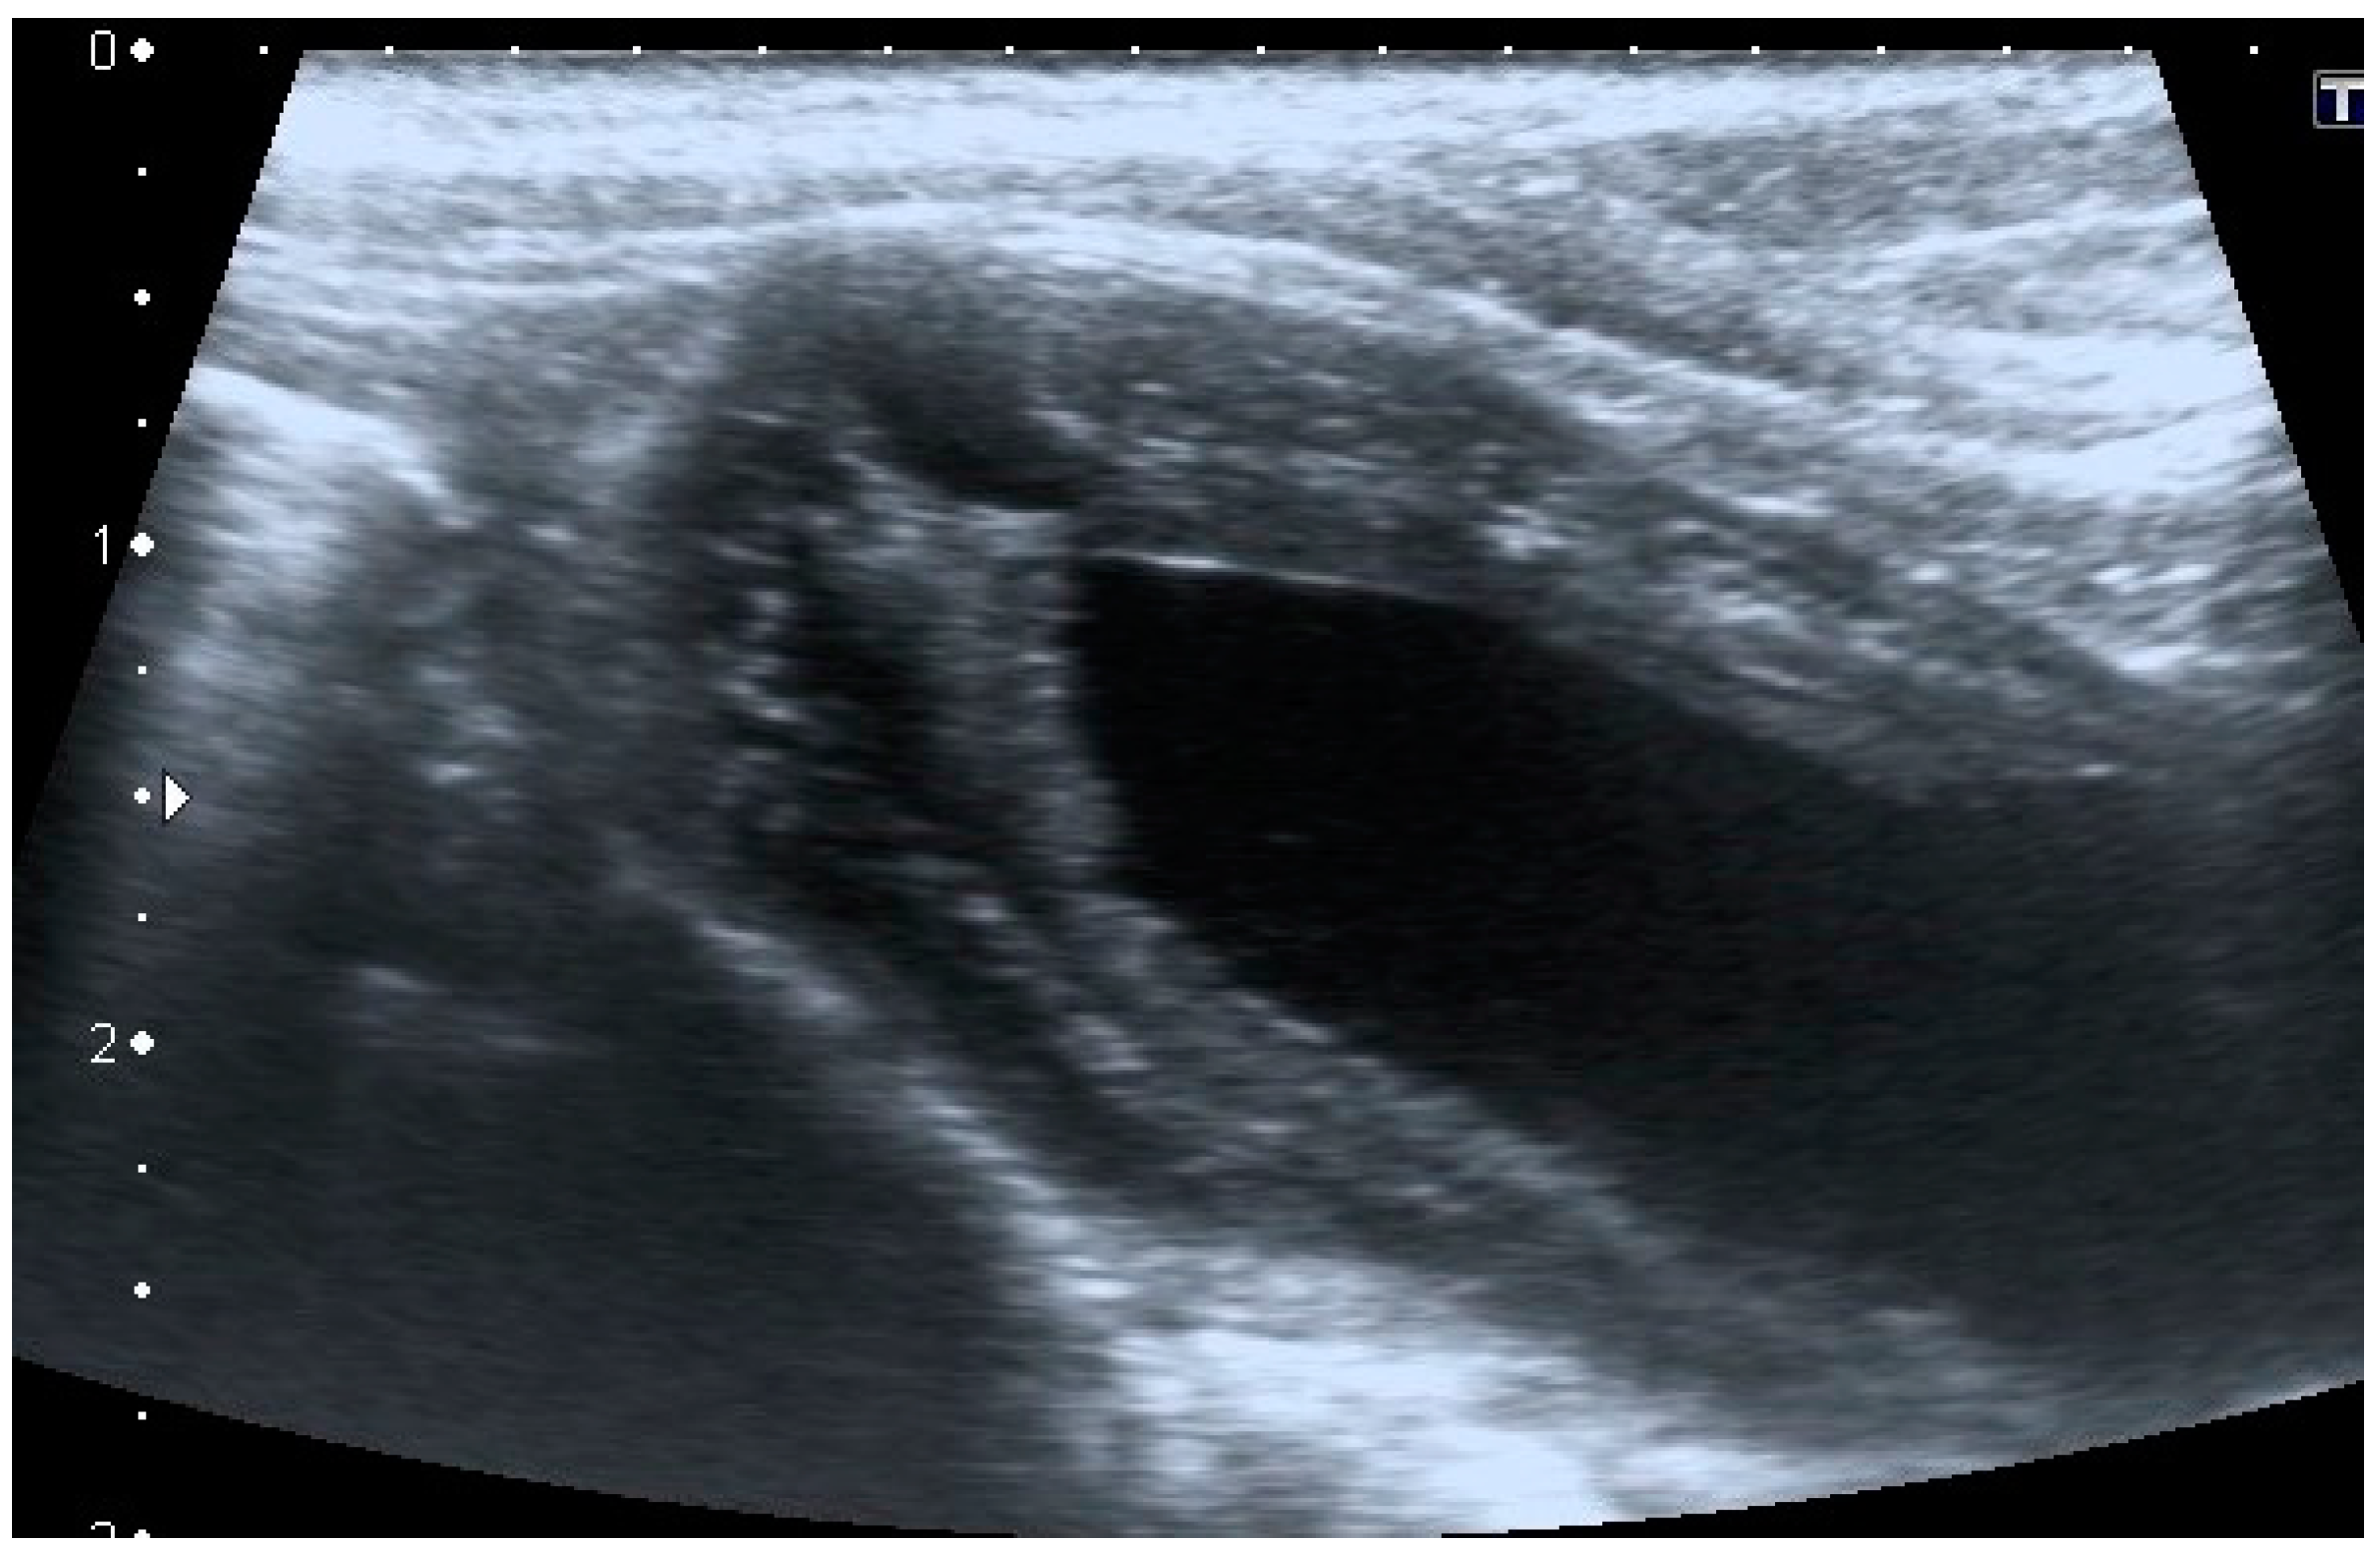

Patent urachus was present in only one mixed-breed dog of 6 months of age. The urachal presented a tubular structure and anechoic content. The formation began from the bladder and ended at the umbilicus (Figure 5).

Figure 5. Longitudinal ultrasound images of a patent urachus in a dog. A tubular structure (≤5 mm diameter) with a small amount of anechoic content extends from the cranio-ventral bladder wall to the umbilical region. Mild reactivity of the peritoneal fat and a small quantity of peritoneal fluid are present in proximity of the urachus. (a) Terminal urachus part reaching the umbilical region; (b) intermediate urachus part; (c) urachus part in continuity with the bladder apex.